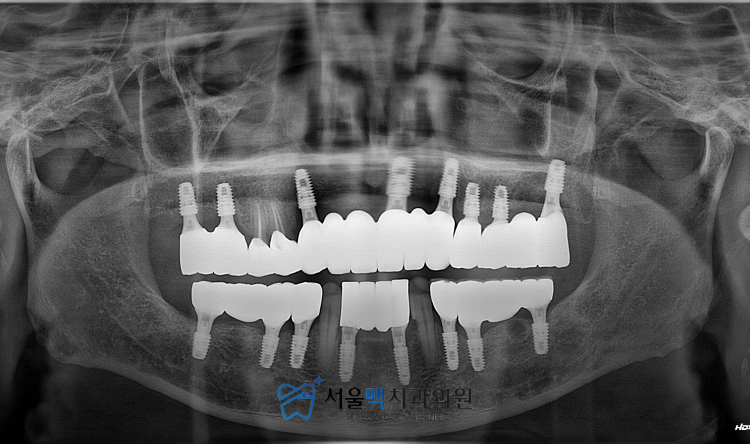

특히 치조골 소실이 심했던 부위에는

부족한 뼈를 보충하기 위한

골 이식술을 병행했는데요.

이는 임플란트를 심는 것을 넘어

향후 환자분이 음식을 씹을 때 발생하는

힘을 견딜 수 있는

튼튼한 기반을 만들기 위함입니다.

상악과 하악 전체를 재건해야 하는

대규모 수술이었던 만큼

위아래 치아의 맞물림인 교합 관계를

설정하는 데 심혈을 기울였습니다.

치아가 대부분 사라진 상태에서

새로운 치아의 높이와 위치를 정하는 것은

매우 정교한 설계가 필요한 작업입니다.

서울맥치과에서는 디지털 장비와

의료진의 숙련된 경험을 결합하여

환자분에게 가장 편안한 위치를 결정하고

그에 맞춰 임플란트를 전략적인 위치에 식립했습니다.

수술 과정에서 식립된 임플란트가

잇몸뼈와 충분히 결합하기를 기다리는

기간 동안에도 환자분의

잇몸 회복 상태를 지속적으로 관찰하였는데요.

치주 상태가 좋지 않았던 환자분일수록

초기 고정력 확보와 감염 예방이 중요하기에

사후 관리에 더욱 세심한 주의를 기울였습니다.

뼈와 인공 뿌리가 안정적으로

골유착 된 것을 확인한 후

환자분의 얼굴 형태와 조화를 이루는

최종 보철물을 제작하여 연결하였습니다.

2026.02.12

이 보철물은 심미적인 만족을 주는 것을 넘어

실제 자연 치아와 유사한 저작력을

발휘할 수 있도록 강도와 형태를

균형있게 설계했습니다.